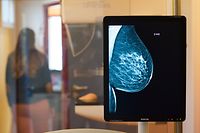

Des divergences sont également notables selon le sexe. Les hommes sont ainsi davantage touchés par le cancer du poumon (26,4%), de la trachée (17%) ou du colon (11%). Le cancer du sein domine en revanche nettement du côté des femmes. En 2013, ce type de cancer représentait 37,9% des 1.119 cas détectés et serait responsable de la mort d'une patiente du cancer sur cinq.

Pour le professeur Berchem, le dépistage reste donc primordial, même en temps de pandémie. «Avoir le covid est une chose, avoir un cancer en est une autre», souligne-t-il. Chaque année, entre 2.000 et 3.000 cancers sont ainsi diagnostiqués au Grand-Duché.